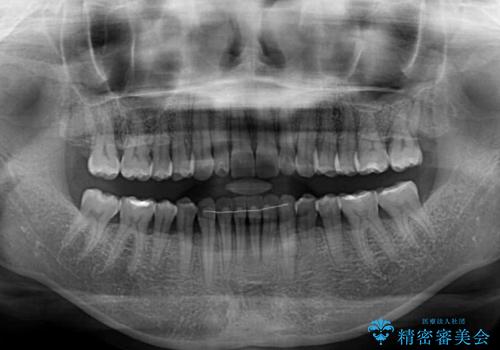

- 前歯の上下スペースによる食べにくさを気にして来院された患者様です。

インビザラインにより上下の前歯の隙間を閉じていくこととしました。

舌の突出癖があると上下前歯にスペースが開くため、矯正治療を機会に舌癖を改善するトレーニングを行ってもらい、矯正治療後の後戻りを防止するように指導しています。